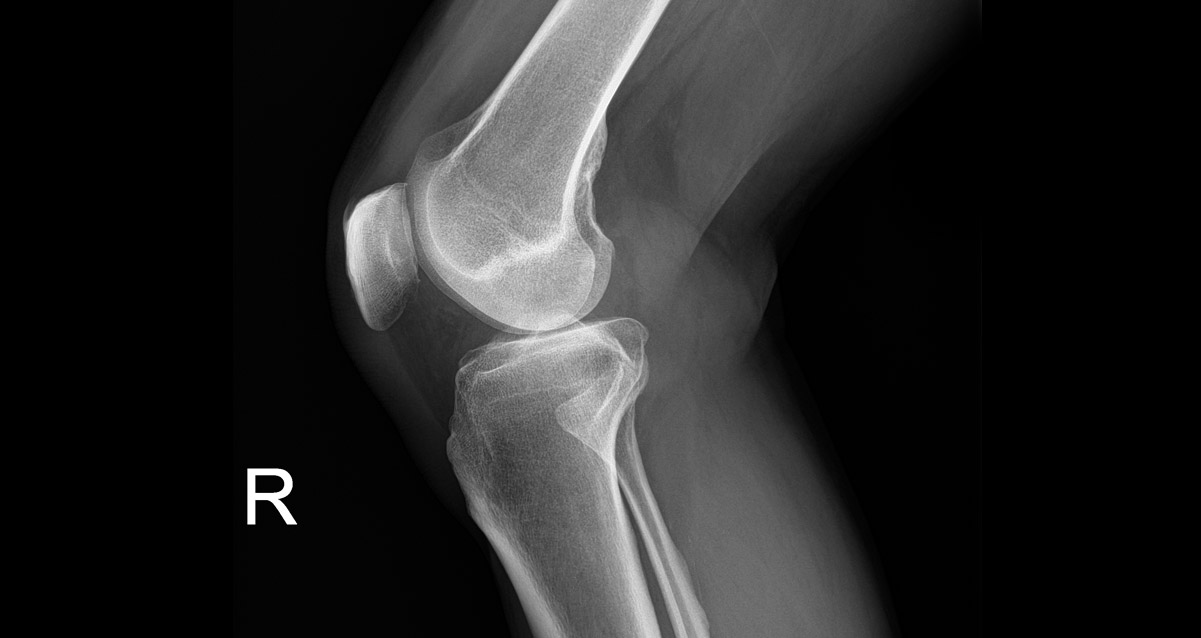

Analysing Knee Osteoarthritis x-rays

How RBknee™ is bringing value: Bispebjerg Hospital, Denmark

Results of study

Patient-centred workflow Enables same day diagnostics for patientsz

Reducing unnecessary MRI examinations Only offering MRIs to the patients who will benefit the most

Increased Standardisation Unified pathway for patients with knee osteoarthritis

We need to open up for using smart technology like the one Radiobotics offers to help save time for reading conventional and less complicated cases